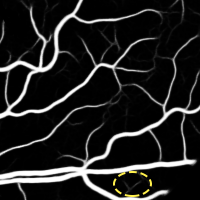

4.2 Validation of the Stationary Wavelet Transform

Having analyzed our Base System, we evaluate the effects of incorporating the SWT into it. The results of each variant are shown in Table 4, while the probabilistic predictions can be seen in Fig. 5. The patches coming from the SWT were concatenated in the input, by varying the total number of input channels. We resorted only to detail coefficients since the goal was to enhance image transitions. We started by concatenating the detail coefficients of the first level in the initial green channel input – BS + . Then, we added those of the second level – BS + + . Finally, only the latter were kept – BS + .

Analyzing the results of the tests performed, we notice that all the alternative strategies improved the performance of the Base System, in terms of Acc and AUC. This means that the use of features based on the wavelet decomposition, whose effectiveness for vessel segmentation is well-known (Soares et al.,, 2006; Zhang et al.,, 2017), is also beneficial when combined with a deep learning methodology. In particular, we see that the first level SWT coefficients used on BS + were less effective than those of the second level applied on BS + . The first level translates spectral information of higher frequencies; this seems to have induced more false positives, as can be seen in Fig. 5. On the other hand, the second level SWT coefficients introduced statistically significant differences to the Base System, in both Acc and AUC, which seems to reinforce the idea that even deep learning methods can benefit from domain knowledge. In fact, they allowed to reduce the combination of false positives and false negatives as we can see in Fig. 5 as well. From now on, we will refer to the best model (BS + ) as Proposed.